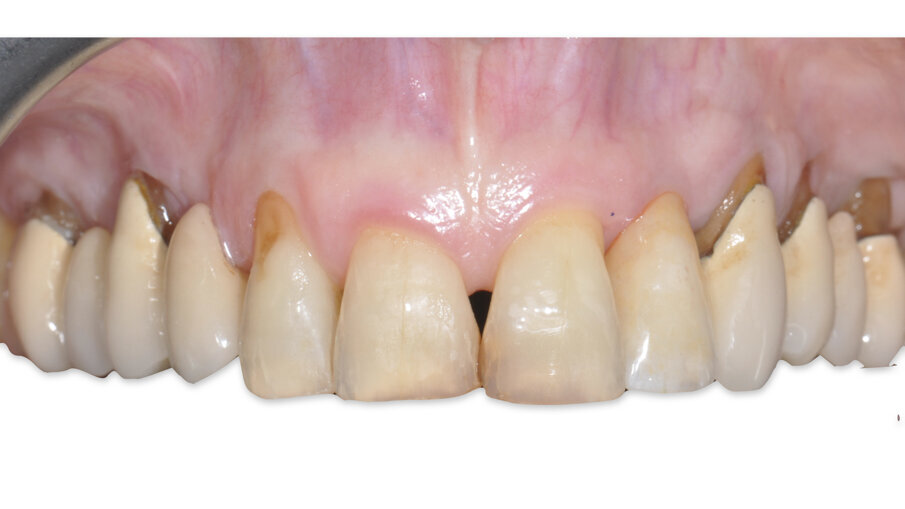

A 7 giorni è stato eseguito un controllo per verificare lo stato dei tessuti gengivali e continuare a motivare la paziente riguardo all’esclusione dai carichi masticatori (Fig. 9). A 90 giorni è stato rimosso il provvisorio per procedere al restauro ceramico. Nonostante la superficie SLActive preveda un accorciamento dei tempi di integrazione, è stato deciso un tempo di attesa convenzionale per accertarsi della stabilità dei tessuti molli perimplantari (Figg. 10-12). È stato eseguito un workflow digitale a partire dall’impronta ottica, fino alla realizzazione di un restauro in Zirconia precolorata e stratificata vestibolare (Dental Direkt 1200 e Creation ZI-CT) su base titanio (Figg. 13, 14). Il restauro è stato consegnato mediante avvitamento a controllo di torque secondo le indicazioni della casa produttrice (Figg. 15, 16).

Fig. 10_Aspetto clinico a 90 giorni.

Fig. 12_Confronto tra la situazione iniziale, quella post-chirurgica e quella al termine del periodo provvisorio.